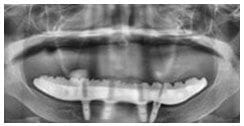

X 光片

術前X光片